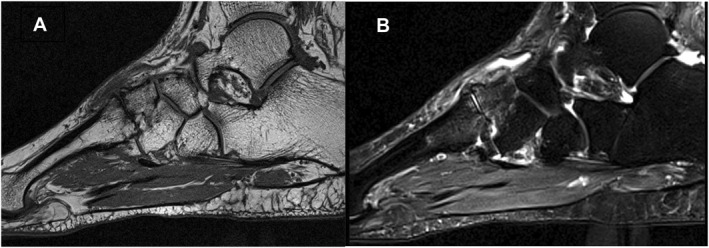

Background: Midfoot pain is common but poorly understood, with radiographs often indicating no anomalies. This study aimed to describe bone, joint and soft tissue changes and to explore associations between MRI-detected abnormalities and clinical symptoms (pain and disability) in a group of adults with midfoot pain, but who were radiographically negative for osteoarthritis.

Methods: Community-based participants with midfoot pain underwent an MRI scan of one foot and scored semi-quantitatively using the Foot OsteoArthritis MRI Score (FOAMRIS). Foot pain and disability were recorded using visual analog scales (VAS) and the Modified-Manchester Foot Pain Disability Index (MMFPDI). Associations were assessed for continuous data using Spearman's Rho, and for categorical data, a Wilcoxon signed rank test. Linear regression was used to explore the association between participant-reported measures and MRI abnormalities, adjusted for age, sex and BMI.

Results: Sixty-one participants (70% female, mean age 48.5 years, median BMI 28.6 kg/m2) were included. Median VAS pain was 31/100 mm (IQR 21-47) and median disability was 30/48 (IQR 26-36). There was a moderate association between midfoot pain severity and the number of joints exhibiting joint space narrowing; adjusted results suggested 31% (95% confidence interval 3%-68%) worse VAS pain with each additional affected joint. Greater numbers of joints with cysts were associated with worse VAS pain [14% (0%-31%)] and disability [1.1 units (0-2.2)]. Effusion/synovitis was associated with MMFPDI pain. No other MRI abnormalities were associated with sex, body mass and foot pain/disability measures. Bone marrow lesions, joint space narrowing, cysts and osteophytes occurred more frequently with age. MRI abnormalities were common, particularly in the talo-navicular joint, first and second cuneo-metatarsal joints. Those with dorsal foot pain had more multi-joint involvement, bone marrow lesions, joint space narrowing and cysts and for those with pain on midfoot movement, bone marrow lesions and cysts were reported.

Conclusions: In people with midfoot pain, MRI-detected features of osteoarthritis and soft-tissue abnormalities were found, clustered in the medial and intermediate cuneiform joints. These features were more common with age but not associated with pain or disability measures. Younger people with dorsal midfoot pain exhibited early signs of bone and joint features of osteoarthritis and we recommend further imaging studies to determine the clinical and diagnostic significance.